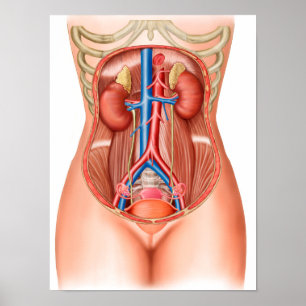

Anatomi i mänskliga organ vykort

Pris23,00 kr

Anatomi i mänskliga organ poster

Pris229,00 kr

Anatomi i mänskliga organ canvastryck

Pris1 425,00 kr

Anatomi i mänskliga organ hälsningskort

Försäljningspris 49,00 kr. Ursprungligt pris 54,00 kr.